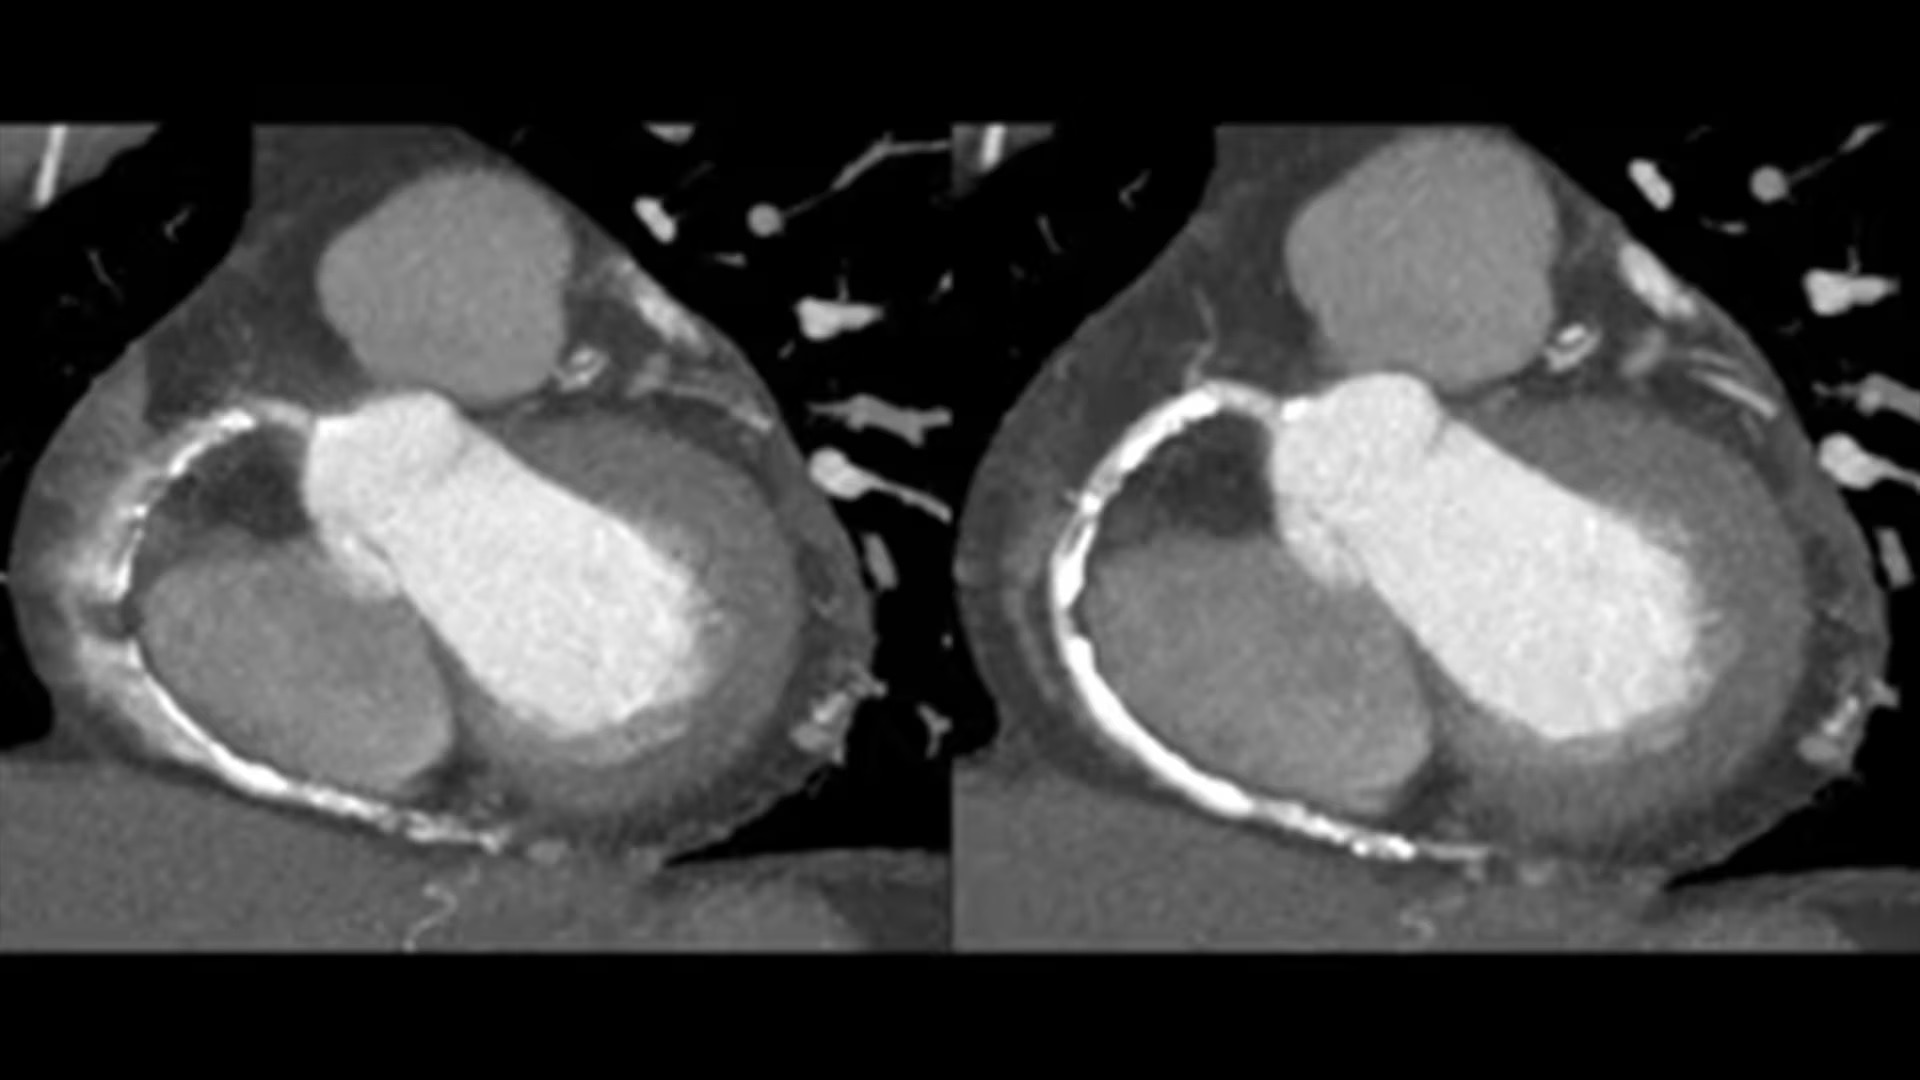

SnapShot Freeze 2

Intelligent and automated whole-heart motion correction for enhanced Cardiac CT imaging.

Motion correction

6x reduction in motion artifacts1

Temporal resolution

19.5 msec effective temporal resolution at 0.23s/rotation gantry speed2

Automated

Whole-heart motion correction